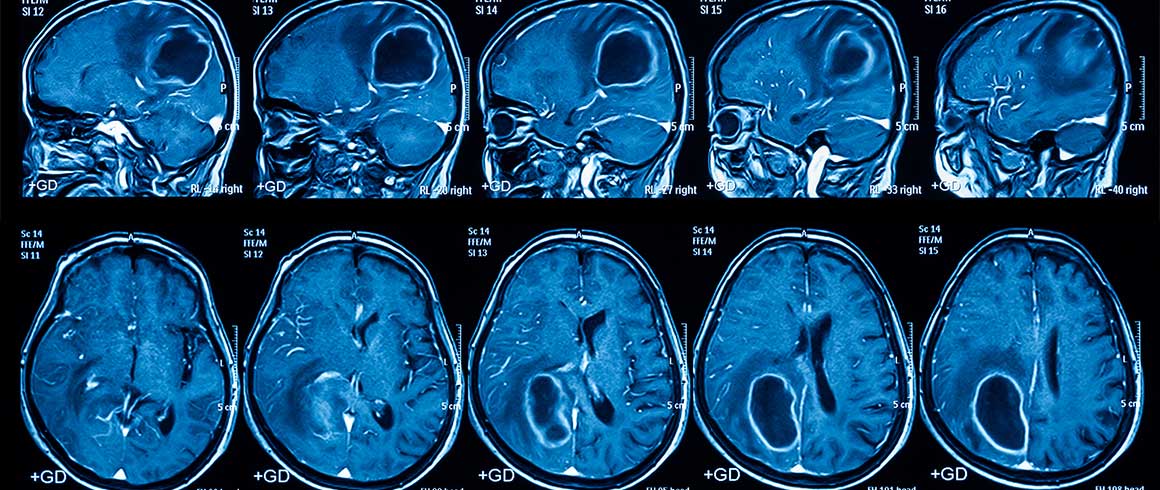

Dalla riproduzione in laboratorio del glioblastoma, il più aggressivo tumore cerebrale, purtroppo ancora oggi senza efficaci terapie, allo studio di cure personalizzate in grado di colpire selettivamente le cellule staminali tumorali che ne favoriscono la recidiva. È questo in sintesi il risultato dello studio realizzato da una equipe multidisciplinare di ricercatori dell’Università Cattolica - Fondazione Policlinico Universitario A. Gemelli di Roma e dell’Istituto Superiore di Sanità e pubblicato sulla prestigiosa rivista scientifica “Neuro-Oncology”.

Il glioblastoma è il tumore cerebrale più maligno e, purtroppo, anche più frequente nell’adulto. In Europa e nel Nord America, la sua incidenza è di 2-3 nuovi casi all'anno su 100.000 abitanti. Non esiste alcun trattamento efficace per una cura completa di questo tumore, né è possibile fare programmi di screening per prevenirlo.

Nonostante i progressi dell’oncologia in campo genetico e molecolare, sono stati ottenuti soltanto miglioramenti limitati della sopravvivenza dei pazienti affetti da glioblastoma negli ultimi decenni. Quasi inesorabilmente, il glioblastoma recidiva nel cervello dopo circa 14-15 mesi dall’intervento neurochirurgico e dalla radio-chemioterapia.

La resistenza del glioblastoma alle cure è dovuta verosimilmente alla presenza di cellule staminali tumorali che invece di dare origine a un tessuto sano producono un tumore. Queste cellule, che rappresentano quindi il reservoir tumorale, sono molto resistenti alle radiazioni e ai farmaci chemioterapici e sono anche in grado di migrare al di fuori del tumore per invadere il tessuto cerebrale, lontano dall’area coinvolta dalla rimozione chirurgica.